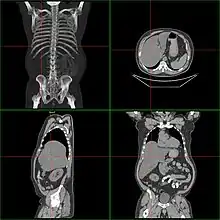

| Computerized tomography of affected person with hepatomegaly | |

Computerized tomography (CT) can give accurate anatomical information for a complete diagnosis.[22]